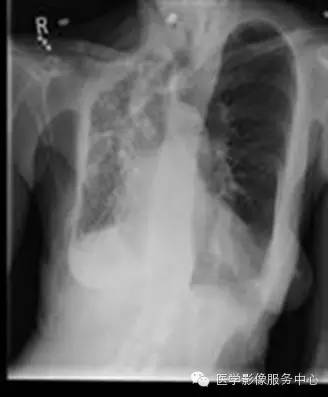

UAPA典型X线表现为患侧肺纹理稀疏肺、容积减小和透光度减低;患侧肺动脉段缺如对诊断UAPA具有重要提示意义,但由于肺纹理稀疏如诊断经验不足多不能明确此征象。胸部X线平片提示病变后,应首选胸部CT平扫进一步检查。